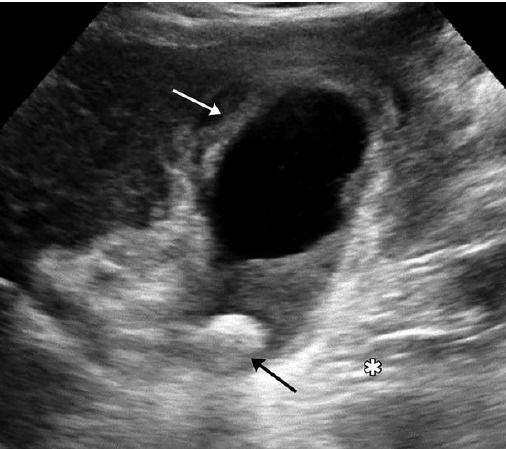

早期胆囊壁充血,而晚期由于囊壁缺血、过度扩张和严重水肿,血流信号无法探测。只有 33% 的坏疽性胆囊炎患者出现超声墨菲斯征阳性,因此超声墨菲斯征阳性因其特异性低和评估困难在诊断可疑急性胆囊炎方面存在局限。当扩大或缩小的胆囊周围出现积液(图 2),或邻近肝实质内出现肝脓肿(图 3),应高度怀疑坏疽性胆囊炎,此时胆囊超声表现为黏膜脱垂、囊壁不对称、隆起、凸入囊腔。

图?2 ?图 A 为60 岁男性坏疽性胆囊炎,右上腹疼痛 7 天,发热,败血症。超声表现为胆囊增大、胆泥淤积(*),胆囊壁不连续(长箭头),黏膜剥离(弯曲箭头),周围相邻肝内可见?4.6 cm×5.5 cm 脓肿(短箭头);图 B 示另一患者胆囊颈部粘膜中断伴胆囊周围积液(c)。胆囊壁增厚,条纹状弱回声带,胆汁淤积

图 3 73 岁男性坏疽性胆囊炎,败血症、肝功能异常、直接胆红素升高。图 A 为超声矢状切面示胆囊轻度增大(*)伴囊壁增厚,胆囊旁肝实质内不规则低回声(短箭头),无血流信号;图 B 为左侧卧位,超声表现为胆囊壁缺损(长箭头)伴邻近肝实质内低回声(短箭头),提示胆囊穿孔和脓肿形成;图 C 为增强 CT 冠状面,示胆囊轻度增大(*),胆囊旁肝实质内不规则低密度区,提示脓肿形成